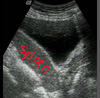

what are the dimensions of this spleen?

is this normal?

long 10.25cm

AP 4.22 cm

a bit small perhaps

what plane was this image taken in?

transverse